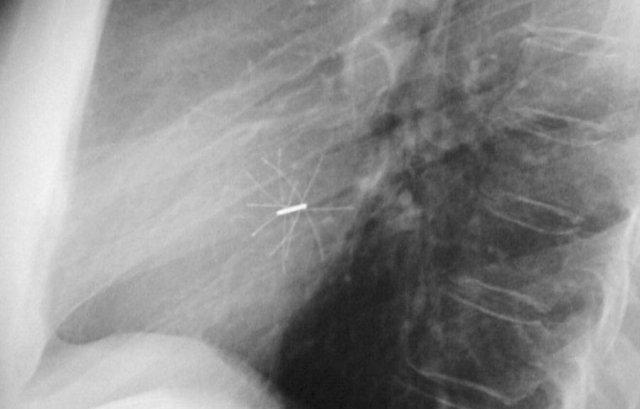

Gãy điện cực

Hình ảnh gãy rõ ràng của một trong các điện cực.

Gãy điện cực kín đáo ở máy tạo nhịp tim hoạt động không bình thường.

Đường gãy cực kỳ kín đáo (mũi tên).